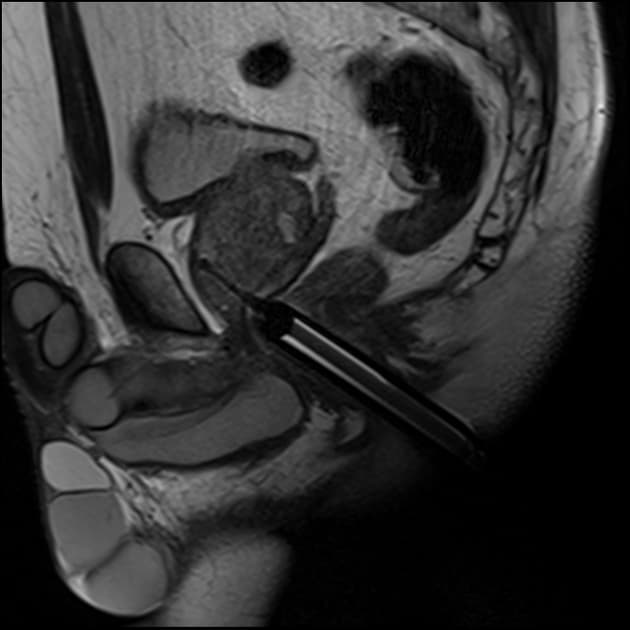

- MRI đa thông số (Multiparametric MRI) tuyến tiền liệt cho thấy một khối u phía trước (anterior tumor) liên quan đến vùng chuyển tiếp (transition zone - TZ) và mô đệm xơ cơ phía trước (anterior fibromuscular stroma - AFS): PI-RADS 5.

- Ghi nhận một vùng tổn thương cần quan tâm lớn, giới hạn trơn láng, đồng nhất (homogeneous) ở phía trước thuộc TZ/AFS. Hình ảnh này biểu hiện dấu hiệu gọi là "dấu hiệu vết than mờ" (smudged or erased charcoal sign).

- Đã thực hiện sinh thiết dưới hướng dẫn của MRI (MRI guided in bore biopsy).

- Đây là một ví dụ về khối u vùng chuyển tiếp (transition zone tumor) biểu hiện dấu hiệu vết than mờ (erased charcoal sign) điển hình.

- Tình trạng này có thể được gọi là PEATS (khối u phía trước tuyến tiền liệt dễ bị bỏ sót - prostate evasive anterior tumor).

Trường hợp này minh họa một ung thư biểu mô tuyến tiền liệt vùng chuyển tiếp (TZ) liên quan đến mô đệm xơ cơ phía trước (AFS). Những tổn thương này thường được gọi là Khối u phía trước tuyến tiền liệt dễ bị bỏ sót (PEATS) vì chúng thường bị bỏ qua khi thăm khám trực tràng bằng tay và sinh thiết dưới hướng dẫn của siêu âm qua đường trực tràng (TRUS) tiêu chuẩn do vị trí nằm ở phía bụng. Trên hình ảnh T2W, chúng thường biểu hiện với 'dấu hiệu vết than mờ', xuất hiện dưới dạng các vùng giảm tín hiệu đồng nhất, giới hạn không rõ thay thế cấu trúc bình thường. MRI đa thông số (mpMRI) đóng vai trò quan trọng trong việc phát hiện, cho thấy hạn chế khuếch tán (DWI cao, ADC thấp) và ngấm thuốc sớm, dẫn đến phân loại PI-RADS 5 trong trường hợp này.